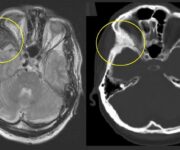

Accanto all’esame clinico, alcuni strumenti di imaging e diagnostica funzionale possono supportare il sospetto diagnostico, soprattutto nei casi dubbi o nelle fasi iniziali. La scintigrafia ossea trifasica rappresenta una delle indagini più sensibili e specifiche per la diagnosi precoce della CRPS. Essa consente di rilevare alterazioni del flusso ematico e del metabolismo osseo anche prima che queste diventino evidenti alla radiografia convenzionale. In particolare, nella fase tardiva della scintigrafia si osserva un aumento dell’uptake dell’isotopo a livello dell’area colpita, indice di una iperattività osteoblastica compatibile con un processo algodistrofico.

Altri esami come la radiografia standard, la risonanza magnetica o l’ecografia possono essere utili per escludere diagnosi alternative o per evidenziare segni indiretti come l’osteoporosi localizzata (atrofia di Sudeck), che si manifesta in fase più avanzata.

Tuttavia, nessun esame strumentale da solo è dirimente: è sempre l’integrazione tra clinica, imaging e giudizio specialistico a guidare la diagnosi definitiva.